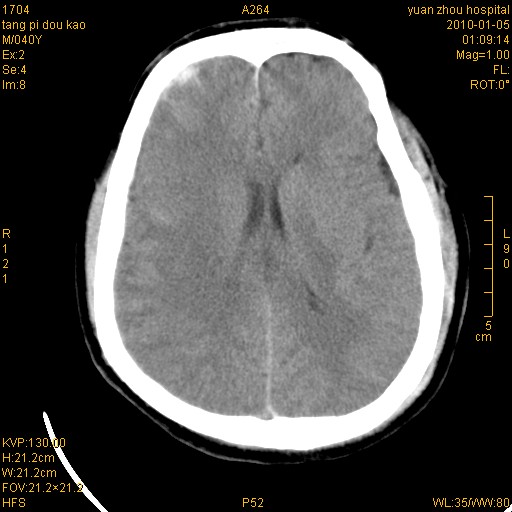

1)左侧颞枕部硬膜外血肿。2)右侧额部硬膜下血肿。3)双侧额叶及右侧基底节下部脑挫裂伤。4)蛛网膜下腔出血。5)脑水肿。6)左侧前组筛窦及左侧额窦炎症。

双侧额叶 右侧大脑脚区多发血肿伴蛛网膜下腔出血!